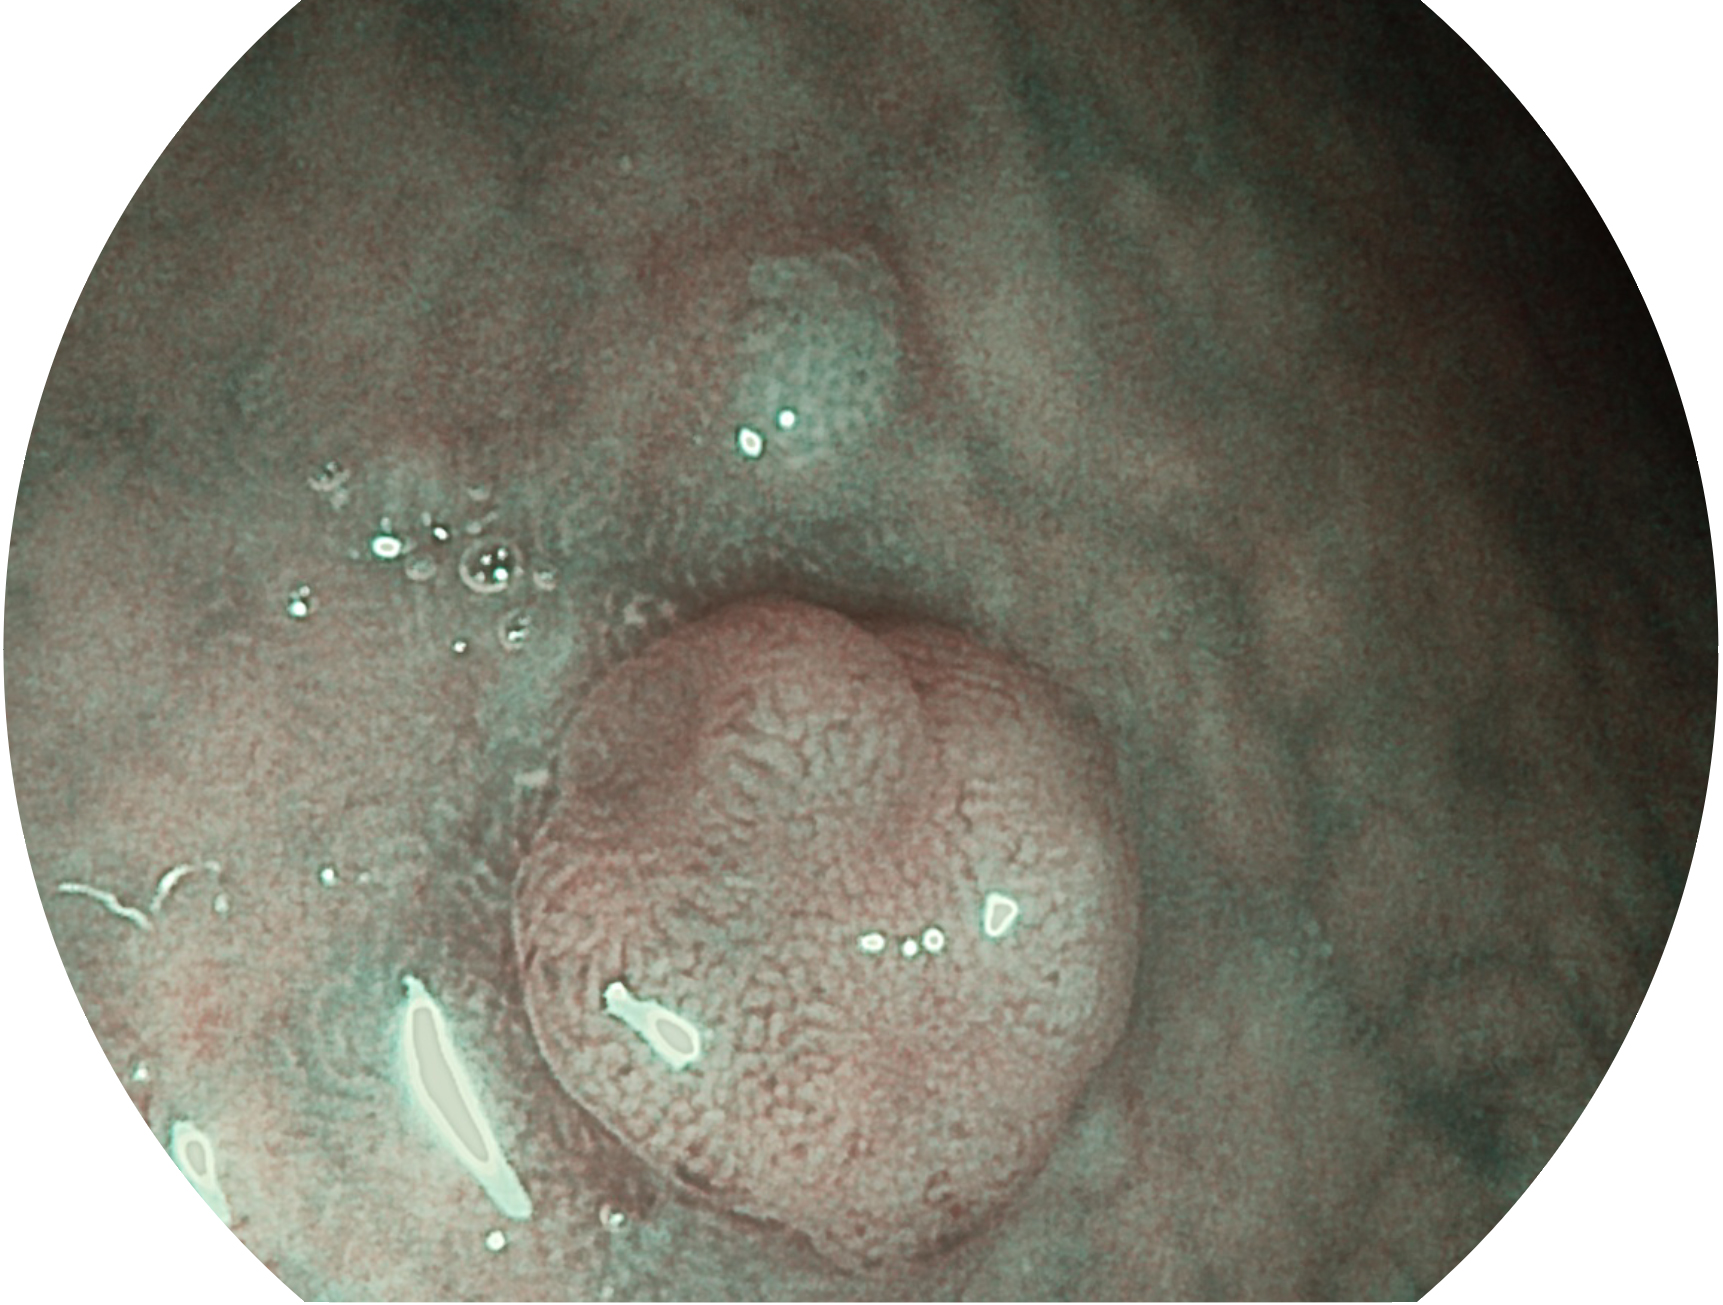

welcome海洋之神新开发的内镜染色技术,主要是基于多波长LED 光源的开发,VLS-55Q 四波长LED 光源是由四个不同颜色的LED光按照相应照明模式所规定的特定发光比例进行合束后形成,合束后形成的照明光的光谱由红光、绿光、蓝光及蓝紫光这四个不同的波段范围构成。具有更高光谱自由度,通过光谱比例的控制,实现了聚谱成像技术,英文全称为“Spectral Focused Imaging, SFI”,缩写为“SFI”和光电复合染色成像技术,英文全称为“Versatile Intelligent Staining Technology, VIST”,缩写为“VIST”。